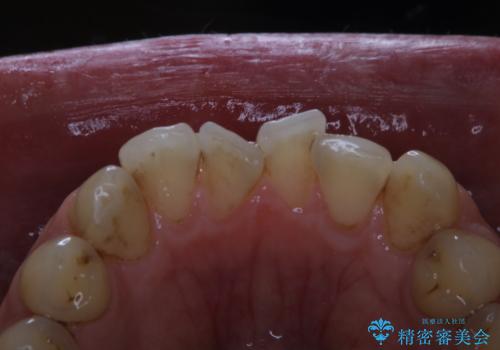

細かいステインをPMTCでOFF

- 歯ブラシをしてもとれないステインが気になるとのことで来院されました。PMTC60分コースを行いました。

毎日丁寧に歯磨きをしていても、日常生活での飲食物などにより着色してしまうことはあります。PMTCでは、歯の表面の凸凹にミネラルを補給して、ツルツルの表面に仕上げます

歯科医院にて、適切な処置を行うことで、長期的に安定したお口の環境が作られます。まずはカウンセリングなどもおススメです。